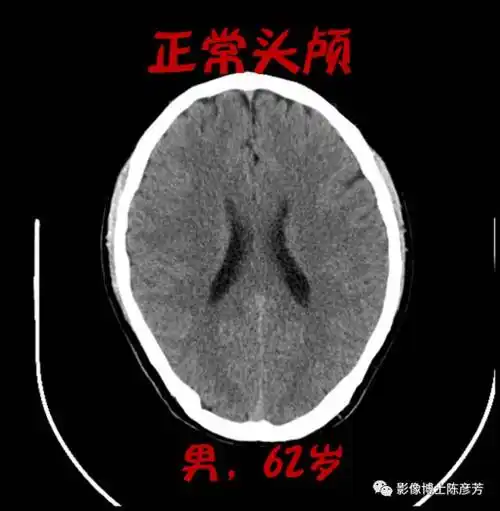

颅脑ct的正常解剖